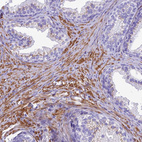

Immunohistochemical staining of human Smooth muscle shows to strong granular cytoplasmic positivity in smooth muscle cells.